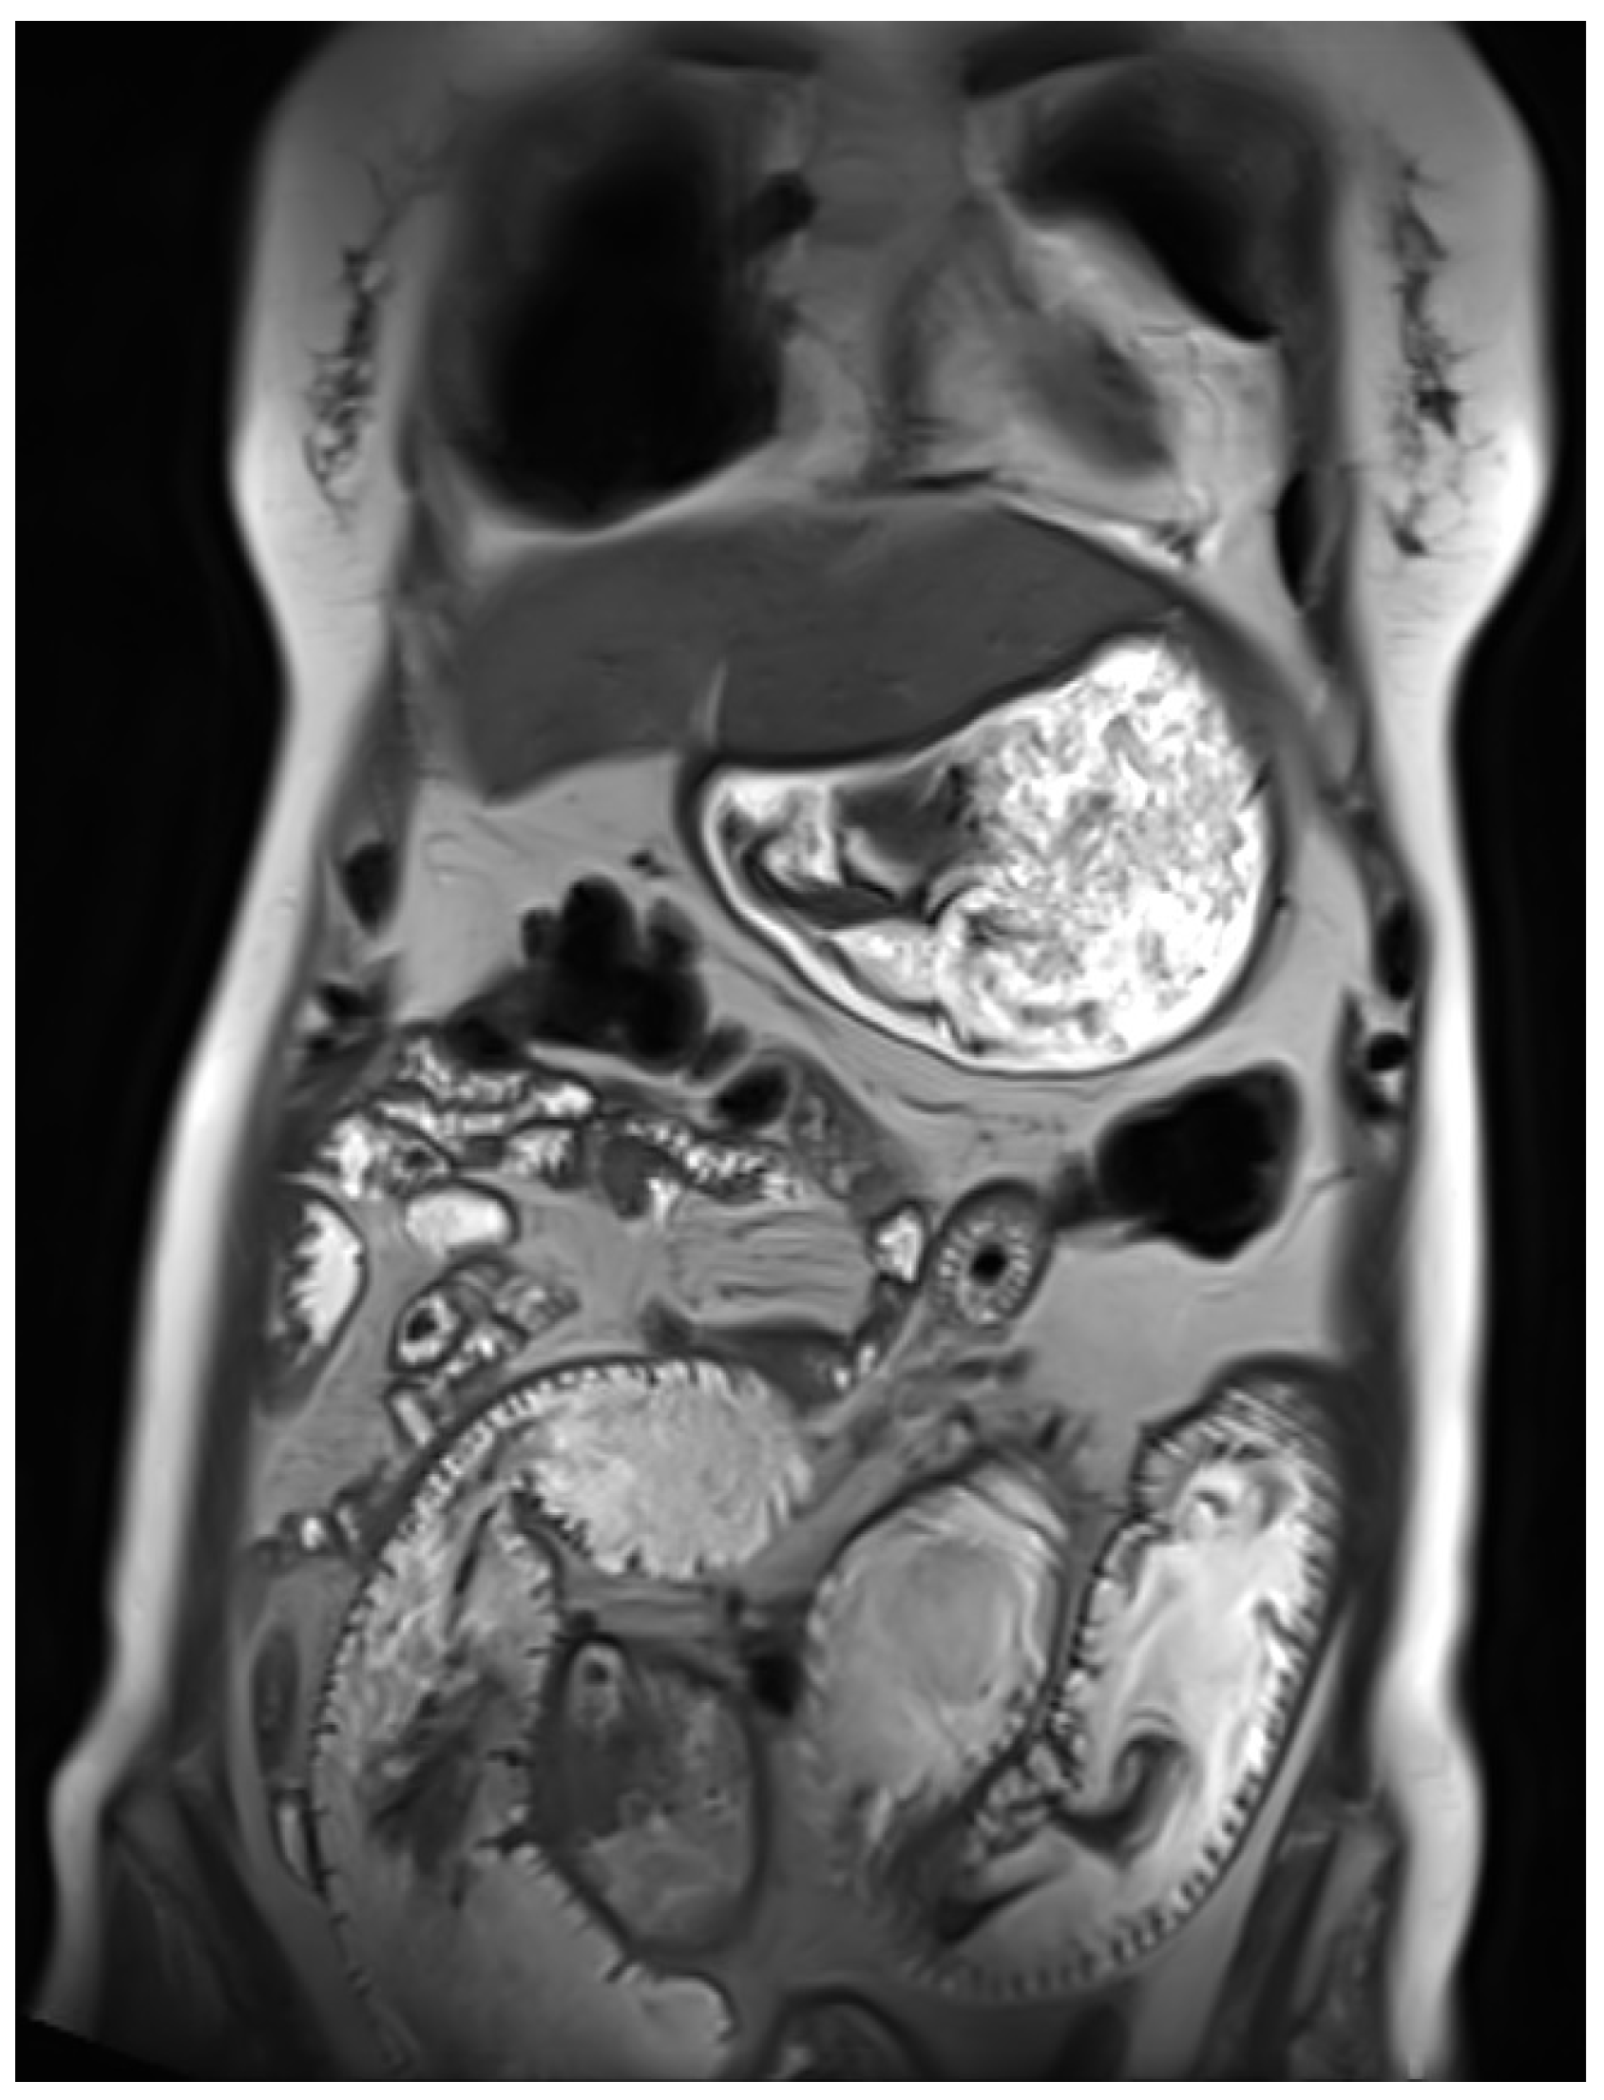

The patient underwent multiple gastroenterological evaluations at different healthcare centres for progressive signs of intestinal obstruction. An entero-MRI was performed, revealing a circumferential, mildly asymmetric, and relatively short segment of thickening at a jejunal loop. This lesion caused significant upstream dilation of the proximal jejunal loops, with a maximal diameter of 5 cm—findings consistent with high-grade intestinal obstruction due to a tight stricture at the jejunal level. No local or distant metastases were identified at that time (Figure 1).

Figure 1. Dilation of intestinal loops on MRI.